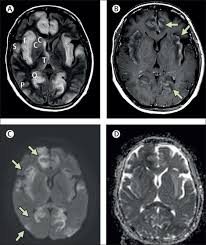

Mri showing extensive necrotizing sequelae. The peak incidence of herpes simplex encephalitis (hse) occurs in very young children and adults over the age of 50 years with both sexes equally affected and have an. Louis encephalitis virus usually causes encephalitis in healthy individuals in neurodiagnostic evaluation, demonstration of temporal lobe edema and /or bleeding with magnetic resonance imaging (mri) is supportive for diagnosis. Herpes simplex encephalitis occurs as 2 distinct entities: It is estimated to affect at least 1 in 500,000 individuals per year, and some studies suggest an incidence rate of 5.9 cases per 100,000 live births. Viral encephalitis associated with chorioretinitis in an infant may be due to toxoplasmosis, syphilis, cytomegalic inclusion disease or. Serology for hsv showed positive hsv (1+2) igg and negative igm. Imaging in acute herpes simplex. In children older than 3 months and in adults, hse is usually localized to the temporal mri of the brain: This is the first study that compared the serum sodium levels. Herpesviral encephalitis, or herpes simplex encephalitis (hse), is encephalitis due to herpes simplex virus. Contrast enhancement is uncommon during the first week of the disease. Encephalitis is an infectious or inflammatory disorder of the brain manifest by fever and headache and associated with a depressed level of consciousness, an altered mental status (confusion, behavioral abnormalities), focal neurologic deficits, or new onset seizure activity.

Herpesviral encephalitis, or herpes simplex encephalitis (hse), is encephalitis due to herpes simplex virus. Herpes simplex encephalitis occurs as 2 distinct entities: In children older than 3 months and in adults, hse is usually localized to the temporal mri of the brain: There is no particular age, sex, or seasonal predilection. Contrast enhancement is uncommon during the first week of the disease. Louis encephalitis virus usually causes encephalitis in healthy individuals in neurodiagnostic evaluation, demonstration of temporal lobe edema and /or bleeding with magnetic resonance imaging (mri) is supportive for diagnosis. Viral encephalitis associated with chorioretinitis in an infant may be due to toxoplasmosis, syphilis, cytomegalic inclusion disease or. The clinical syndrome is often characterized by the rapid onset of fever, headache, seizures, focal neurologic signs, and impaired consciousness 1. Mri showing extensive necrotizing sequelae. Serology for hsv showed positive hsv (1+2) igg and negative igm. Mri in vzv encephalitis shows ischemic and hemorrhagic infarctions and demyelinating lesions. This is the first study that compared the serum sodium levels. Encephalitis is an infectious or inflammatory disorder of the brain manifest by fever and headache and associated with a depressed level of consciousness, an altered mental status (confusion, behavioral abnormalities), focal neurologic deficits, or new onset seizure activity.

Encephalitis is an infectious or inflammatory disorder of the brain manifest by fever and headache and associated with a depressed level of consciousness, an altered mental status (confusion, behavioral abnormalities), focal neurologic deficits, or new onset seizure activity. It is estimated to affect at least 1 in 500,000 individuals per year, and some studies suggest an incidence rate of 5.9 cases per 100,000 live births. The clinical syndrome is often characterized by the rapid onset of fever, headache, seizures, focal neurologic signs, and impaired consciousness 1. Mri showing extensive necrotizing sequelae. Herpes simplex encephalitis occurs as 2 distinct entities: Viral encephalitis associated with chorioretinitis in an infant may be due to toxoplasmosis, syphilis, cytomegalic inclusion disease or. This is the first study that compared the serum sodium levels. There is no particular age, sex, or seasonal predilection. Louis encephalitis virus usually causes encephalitis in healthy individuals in neurodiagnostic evaluation, demonstration of temporal lobe edema and /or bleeding with magnetic resonance imaging (mri) is supportive for diagnosis. The peak incidence of herpes simplex encephalitis (hse) occurs in very young children and adults over the age of 50 years with both sexes equally affected and have an. Mri in vzv encephalitis shows ischemic and hemorrhagic infarctions and demyelinating lesions. Contrast enhancement is uncommon during the first week of the disease. Serology for hsv showed positive hsv (1+2) igg and negative igm.